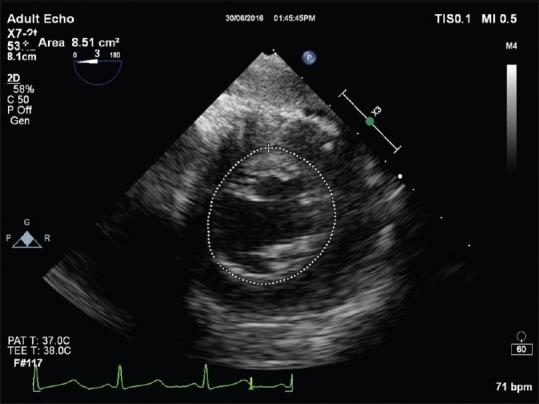

Left ventricular global systolic function assessment by echocardiography.

The left ventricle, with its thickened myocardial walls, unlike the right ventricle has no measurable geometric shape. It has a conical apex and its function quantification, needs intensive, 2D, 3D and M mode transesophageal echocardiography, which is described in this review.